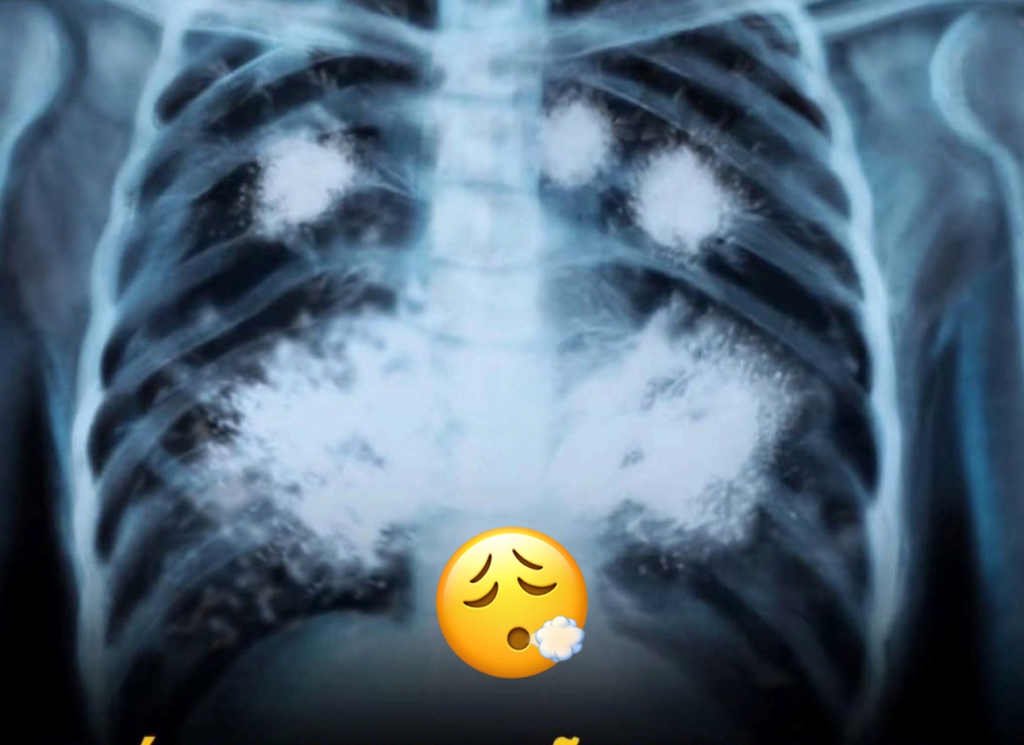

En la actualidad, el uso de los dispositivos de vapeo o VAPE ha ganado una popularidad alarmante entre los jóvenes. Con una edad promedio de inicio cercana a los 18 años, muchos adolescentes y jóvenes adultos experimentan con estos productos creyendo que son una alternativa más segura al tabaquismo tradicional. Sin embargo, los efectos en la salud pueden ser devastadores, como demuestra el caso de un joven de 20 años que ha estado usando VAPE durante dos años y cuyos pulmones presentan características similares a los de una persona de 60 años. A continuación, exploraremos las consecuencias del uso de VAPE y cómo este hábito afecta la salud pulmonar.

El caso del joven de 20 años es un claro ejemplo de los peligros de usar VAPE. Sus pulmones, que muestran daños comparables a los de una persona mucho mayor, revelan que este hábito puede ser extremadamente perjudicial. A continuación, se enumeran algunas de las consecuencias más graves del uso de estos dispositivos:

El uso continuo de VAPE puede llevar a problemas respiratorios crónicos, como la bronquitis y el enfisema. La inhalación constante de aerosoles nocivos puede irritar las vías respiratorias, causando inflamación y daños a largo plazo en los pulmones.

Reducción de la Capacidad Pulmonar

El daño a los tejidos pulmonares puede resultar en una disminución significativa de la capacidad pulmonar. Esto significa que el cuerpo no puede absorber suficiente oxígeno, lo que puede afectar el rendimiento físico y la calidad de vida en general.